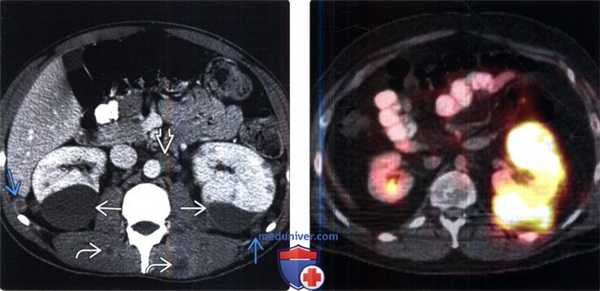

(Слева) КТ с контрастированием, аксиальная проекция: у мужчины 21 года вследствие метастатической меланомы выявлены двусторонняя субкапсулярная гематома почки, паранефральные узелки мягкой ткани, забрюшинная лимфаденопатия и поражение мышц.

(Справа) В левой почке и околопочечном пространстве выявлена ФДГ-положительная опухоль, представляющая собой гематогенные метастазы меланомы в забрюшинное пространство. ПЭТ/КТ—идеальный метод визуализации ФДГ -положительных опухолей, так как часто позволяет обнаружить метастазы скрытых локализаций и в лимфатических узлах нормальных размеров.